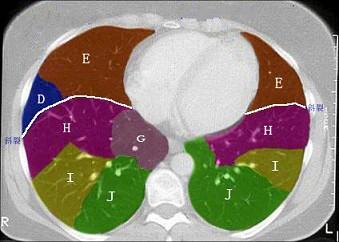

结合肺段模式心室层面(如图),选出右肺上叶的组成 ( )A.AB.A+BC.A+B+CD.A+B+C+DE.A+B+C+D+E

问题 结合肺段模式心室层面(如图),选出右肺上叶的组成 ( )

选项 A.A B.A+B C.A+B+C D.A+B+C+D E.A+B+C+D+E

答案 C